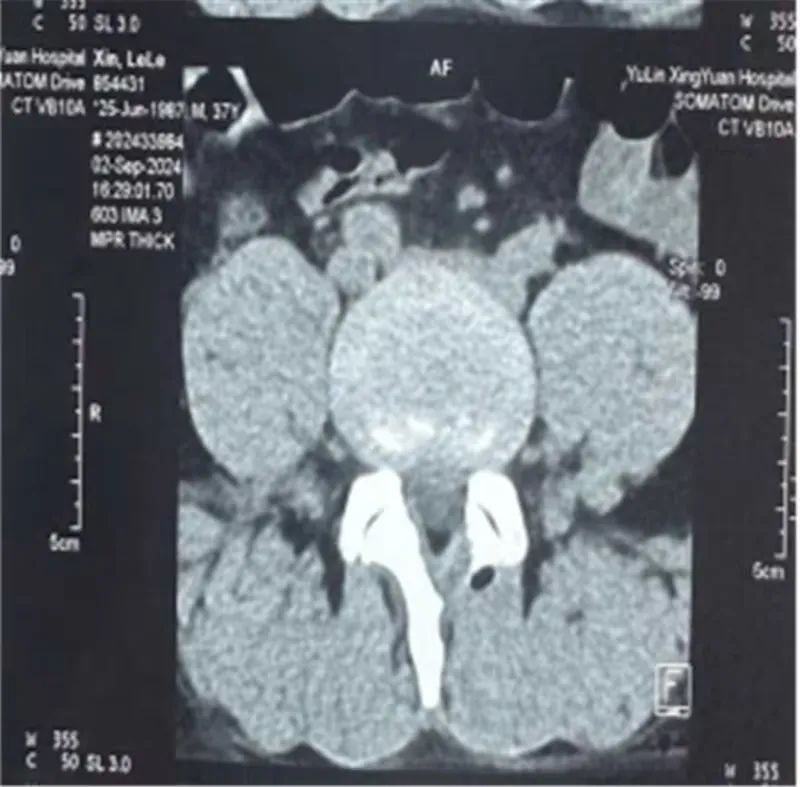

37岁的辛某某,腰臀部酸胀1年,左下肢放射性疼痛1月,曾在当地医院诊断为腰椎间盘突出症给予理疗、射频消融等治疗后症状缓解不明显,近1月来出现左下肢放射性疼痛,从臀部放射至大腿后侧、膝关节、小腿外侧,疼痛进一步加重,严重影响到患者的日常生活。不能下地活动,为寻求进一步治疗,来到市星元医院就诊。经过专科查体及影像学辅助检查,患者被诊断为腰椎间盘突出症、腰椎管狭窄症。邢永军主任医师团队综合评估患者病情,结合患者年龄、椎管狭窄程度、椎间盘退变程度、椎间隙高度等各项指标,经与患者充分沟通,开放手术创伤太大,单轴内镜受灵活性所限,不一定能够达到手术目的,“AUSS是传统脊柱手术内镜化方案,兼具开放手术和内镜手术的优势,且创伤比双通道的UBE手术更小,是目前最好的选择!,制定了“AUSS关节镜辅助单孔脊柱手术”的治疗方案。术中,医生通过可视化内镜辅助对患者狭窄的椎管进行减压、突出椎间盘进行摘除,对破裂的纤维环进行缝合,提高患者术后生活质量,术后患者恢复良好。下肢放射性疼痛完全消失。